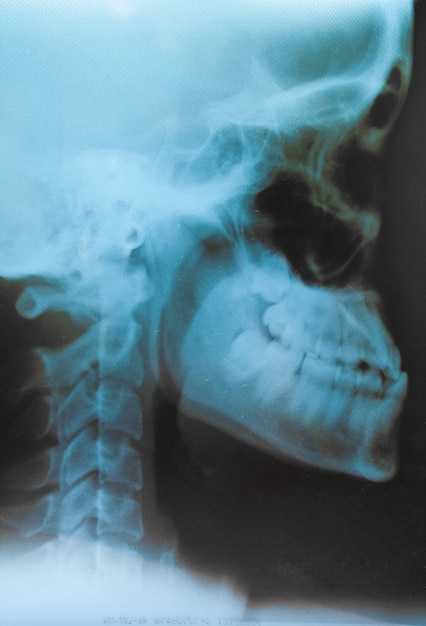

Особенности и процесс проведения рентгена черепа в медицинской практике

Метод визуализации, связанный с получением рентгеновских снимков структур головы, предназначен для диагностики различных заболеваний и нарушений. Этот способ позволяет быстро и точно оценить состояние костей и мягких тканей.

При наличии черепно-мозговой травмы, боли в голове, подозрении на перелом костей основания черепа следует выполнить рентгенографию. Дополнительные показания включают наличие новообразований или подозрений на их возникновение, инфекции в области головы, а также аномалии развития. Исследование необходимо также при оценке состояния после хирургических вмешательств, связанных с челюстью или лицевой частью.

При неясных неврологических симптомах, таких как потеря сознания, судороги или изменения в поведении, стоит обратиться к этому методу диагностики. Он применяется для оценки состояния при подозрении на внутричерепное кровоизлияние и может помочь выявить отеки.

При анализе снимков важно обратить внимание на следующие ключевые моменты:

- Симметрия: Проверьте, равны ли размеры обеих половин. Ассиметрия может указывать на патологии.

- Кости: Оцените целостность структуры. Наличие трещин или повреждений должно вызывать настороженность.

- Тени: Обратите внимание на ненормальные области затемнения или осветления, они могут говорить о наличии опухолей или других образований.

- Суставы: Изучите суставные пространства. Их сужение может указывать на воспалительные процессы.

Необходимо сопоставлять полученные данные с клиническими проявлениями для более точной оценки состояния. Также важно учитывать возраст пациента для интерпретации нормальных анатомических изменений.

Интерпретация зависит от целей исследования: диагностика травм, опухолей или заболеваний. Уделите внимание каждому элементу снимка для получения максимально точного результата.